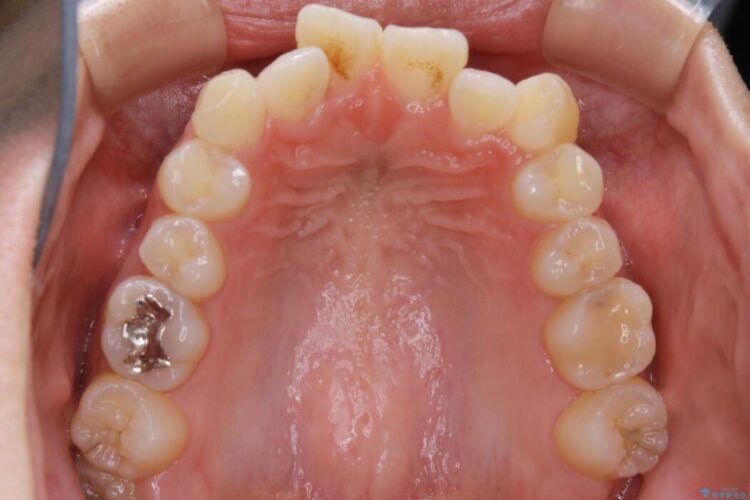

特に前歯部分に90度近く捻転した歯、斜めに生えている歯などによる歯列のがたつき、正中のズレが目立っていました。

奥歯から遠心移動とディスティング(歯の側面を僅かに削る)を行うことで歯列を整えるスペースを確保し、患者様のご要望からインビザライン装置での矯正を計画しました。